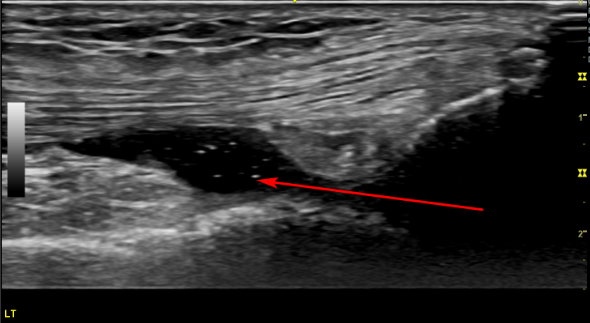

해당 환자분의 양구혈

그런데 이 환자분은 정상 초음파와 다른 모습이죠?

빨간 화살표 부분이 까맣게 물이 찬 것이 보입니다.